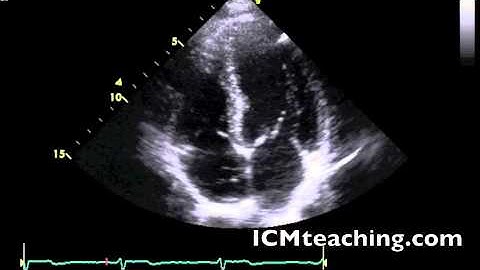

Echocardiogram Apical Four Chamber View - Loop